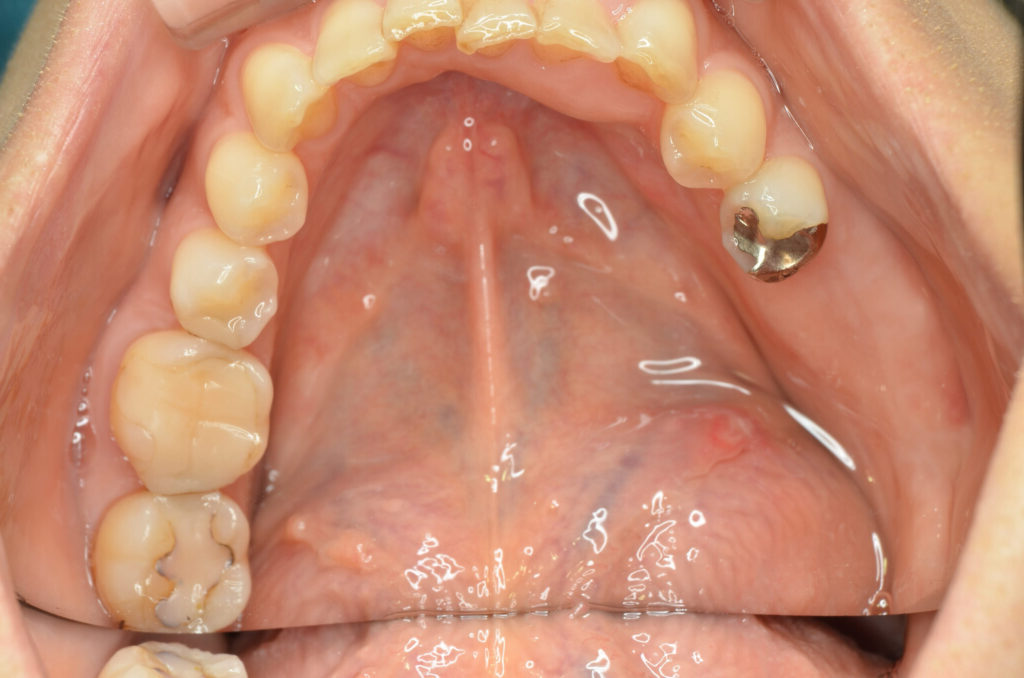

奥歯2本のインプラント

Before

治療内容

インプラント2本・骨造成併用

治療期間・回数

約4ヶ月・約4回

費用

880,000円

治療のリスク

外科手術が必要になるため、患者様に体力的な負担がかかる。